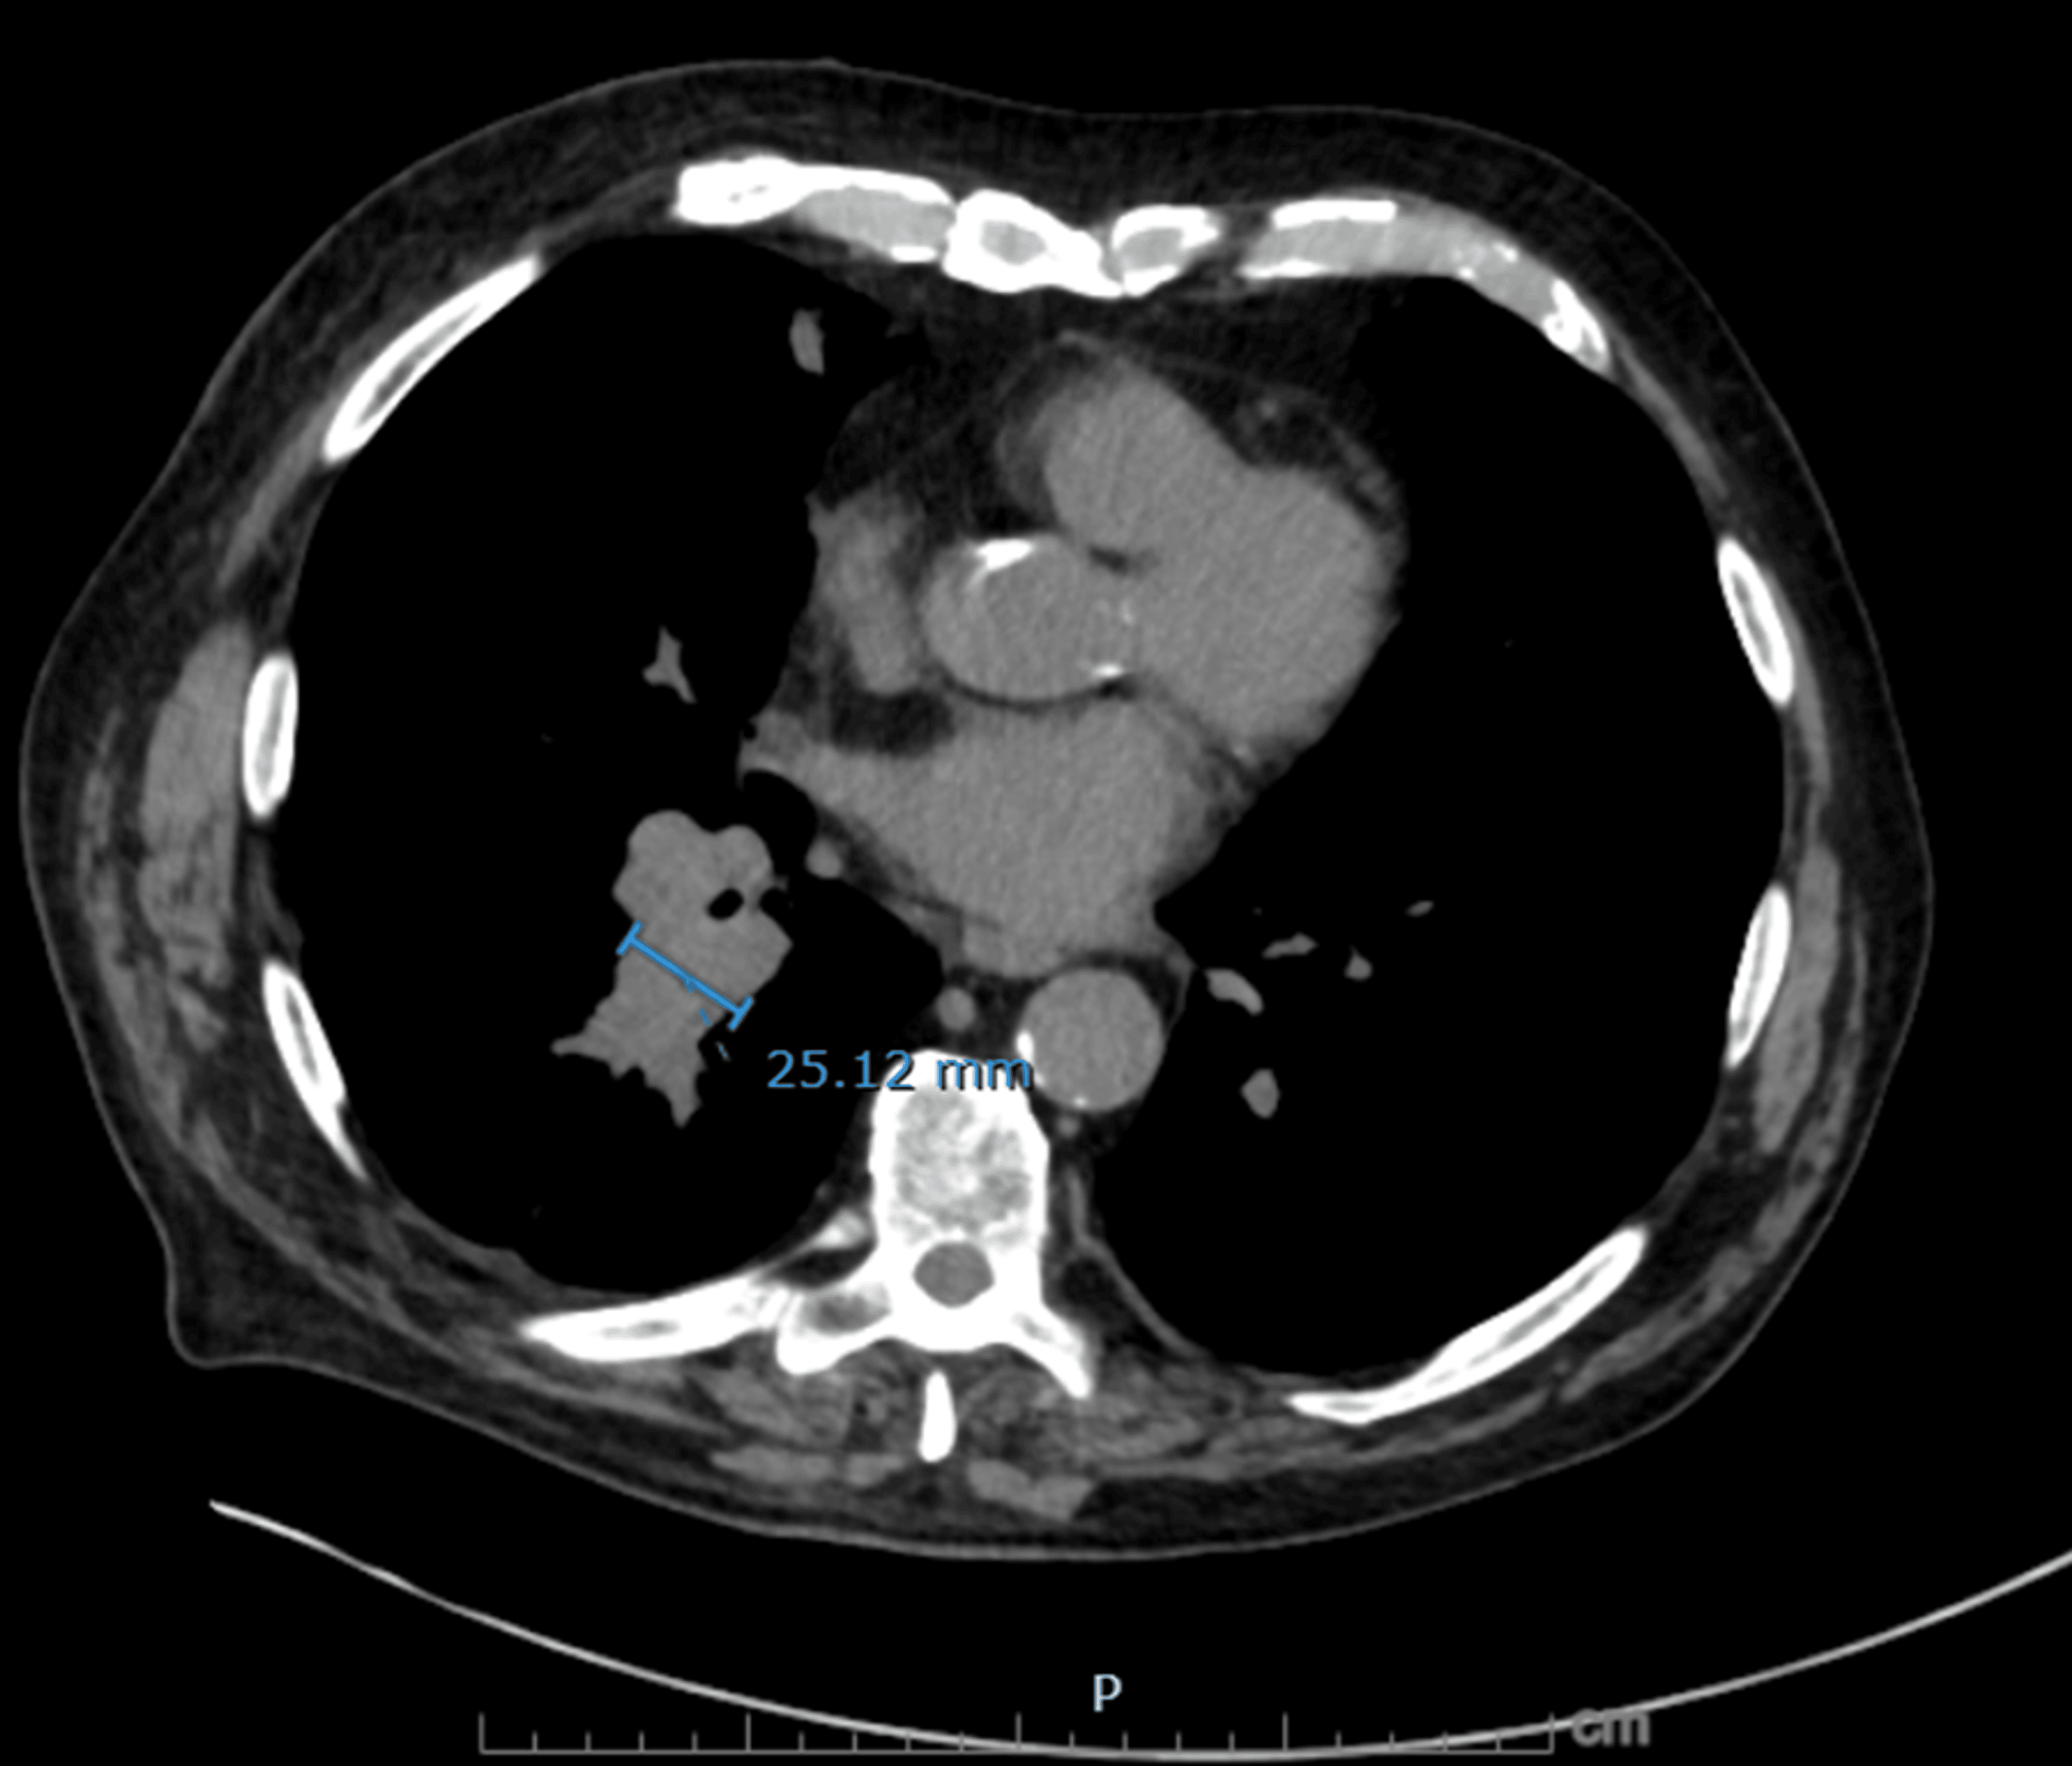

Figure 5: Axial non-contrast CT chest showing right infrahilar mass-like fullness

Soft tissue density in the right lower lobe infrahilar region measuring up to 25 mm in transverse diameter, concerning for primary malignant involvement.